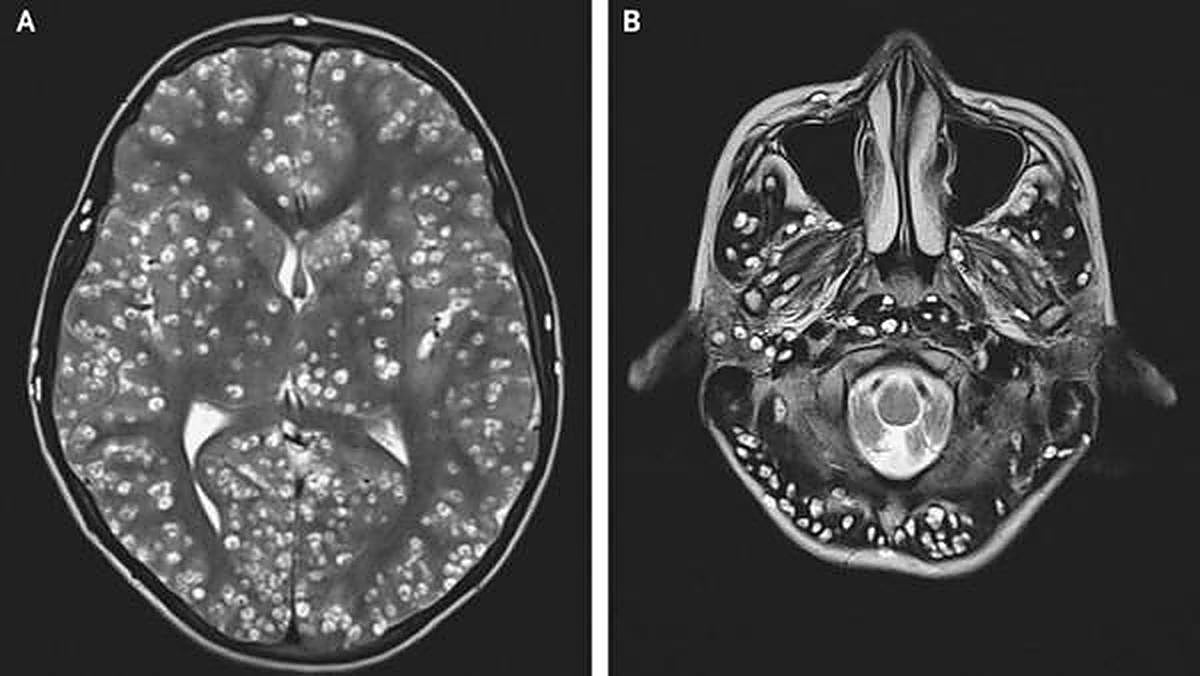

Imagen de la resonancia practicada al joven

Un joven de 18 años perdido la vida como consecuencia de una plaga de tenias parasitarias de cerdo en su cerebro y en la zona de la ingle. El chico llevaba varios días aquejado de dolores en la cabeza y convulsiones, presentaba hinchazón en su ojo derecho y fue acompañado por su familia hasta el hospital de Faridabad, en la India. Los médicos hicieron un examinaron al joven con una resonancia y encontraron, para su asombro, como el joven tenía la corteza cerebral recubierta de pequeños quistes según un informe publicado en “The New England Journal of Medicine”.